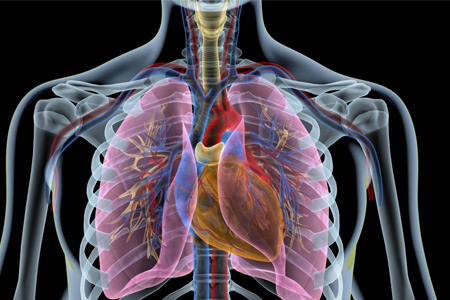

癌症是全球公認的一大公共健康問題,其中肺癌又是癌症中的第一殺手。肺癌的發病率和死亡率在所有癌症中均居前列,給人們的生命健康帶來了嚴重威脅。本文将詳細介紹肺癌的基本知識、危險因素、預防措施等方面的内容,幫助大家更好地了解和應對這種疾病。

肺癌是一種發生在肺部的疾病,其病理類型包括非小細胞肺癌和小細胞肺癌兩種。肺癌可能發生在肺部的任何部位,但大多數肺癌發生在肺的支氣管上皮細胞。肺癌的發生與吸煙、空氣污染、職業暴露等因素密切相關。